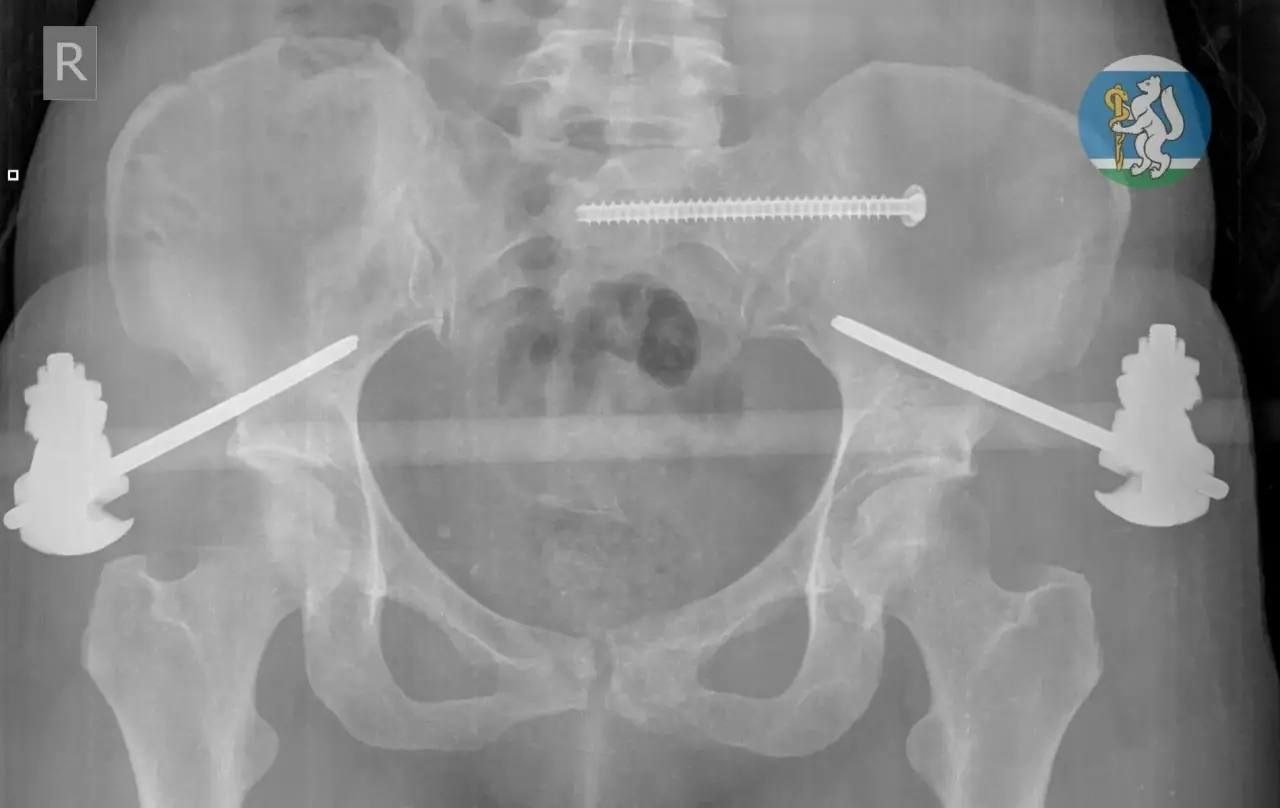

Женщина (36 лет) выпала во время мытья окна. Ее доставили в Городскую больницу №36, где диагностировали черепно-мозговую травму, повреждение позвоночника, множественные переломы таза и открытые переломы ноги – с такими травмами большинство пострадавших не доживают даже до приезда скорой.